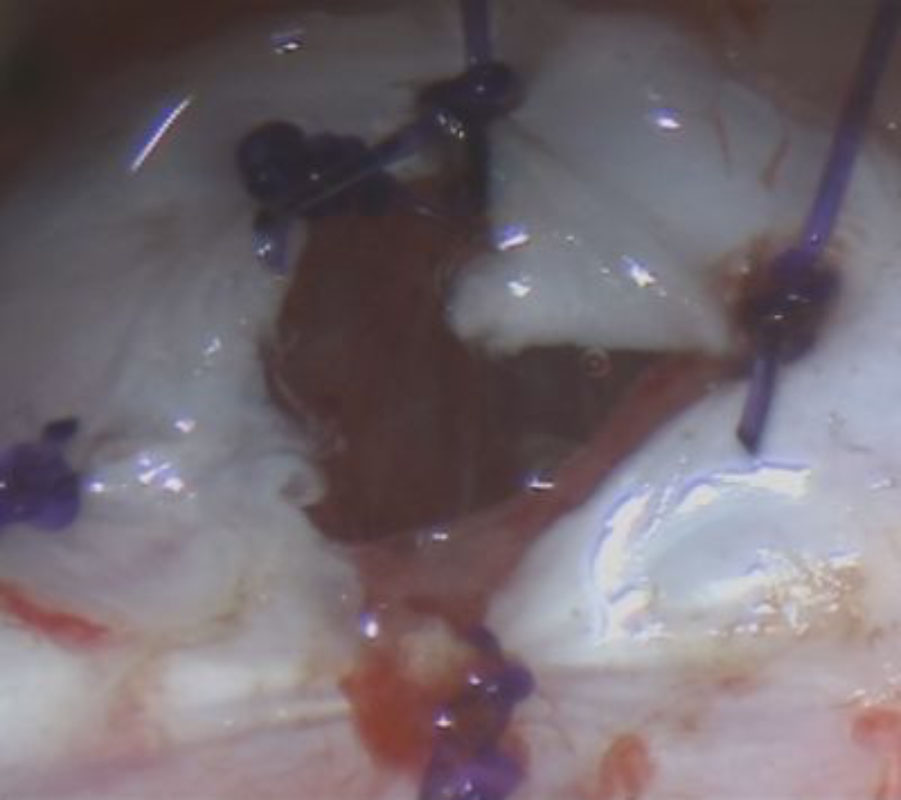

No.’25_48 摘出 前

No.’25_48  摘出 中

No.’25_48 摘出 後